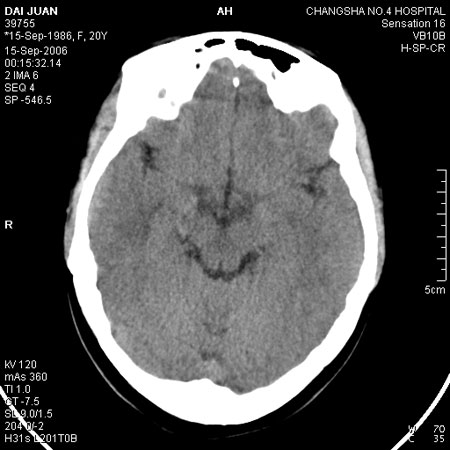

请问各位战友:图示箭头处是否为颅骨骨折?

病史:患者,女,20岁.头部及腹部外伤20分钟.伤后昏迷,无呕吐.头及右侧腰背部疼痛,双侧瞳孔等大,

右肾区叩痛.其它无异常.患者家属否认原有外伤史.

请大家看看是否为颅骨骨折.还是正常变异,或为陈旧骨折.谢谢.

枕骨的线样低密度影锐利、清晰,但正好位于矢状缝的位置,局部无明显软组织肿块,相临及对冲部位脑实质亦无出血及挫裂伤表现。

单就这几层暂不考虑骨折,建议上传完整图片。

枕后部及左侧颞枕部边缘锐利的线样低密度影,局部软组织无异常,左侧乳突蜂房密度均匀,硬膜下及脑实质内未见出血灶,考虑为正常变异。

正常颅缝发育变异,我遇到过没有外伤史的一个病人,同本病例一样,考虑变异,建议随访复查。

未见异常。

绝对不是新鲜骨折!!!!

考虑正常变异!!

未见明显骨折征象。